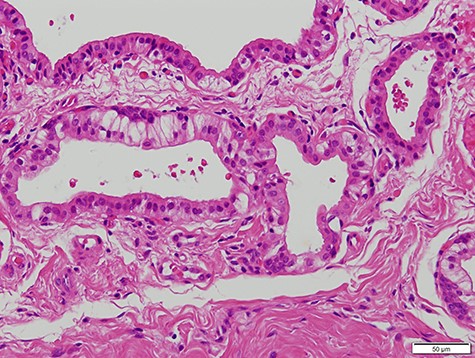

A 63-year-old man was referred to our hospital for treatment of a nodule on his tongue in May 2003. His medical history included Wolff–Parkinson–White syndrome and atrial fibrillation, both of which were controlled adequately by his primary care physician. Physical examination revealed very slight swelling at the right edge of his tongue. The patient reported some spontaneous pain. It was diagnosed as inflammation of the foliate papilla; the patient was followed-up with a gargle prescription. In September 2005, an elastic soft mass, 4 mm in diameter, was observed along the right edge of his tongue (Fig. 1). It was clinically diagnosed as a benign tumour and removed under local anaesthesia. Microscopically, the lesion was composed of multiple cysts of various sizes and shapes, with or without papillary intraluminal short projections (Fig. 2). Many cyst cavities contained eosinophilic fluid. The lesion was well-delineated, but the capsular structure was ill-defined. The stroma was fibrous connective tissue without lymphocytic components. The cystic cavities were lined by a bilayered epithelium composed of luminal columnar cells and basal cuboidal cells. Both luminal and basal epithelial cells were eosinophilic; some clear cells were seen (Fig. 3). Mitotic figures and cellular atypia of epithelial cells were not seen. Immunohistochemically, both luminal and basal cells were CAM5.2+, basal cells were p63+, apical half of the luminal cells were 34βE12+, and the liminal surface was CEA+. The specimen was diagnosed as cystadenoma, based on the histopathological findings.

Micrograph showing the cystic cavities lined by a bilayered epithelium (haematoxylin–eosin stain, 200×).